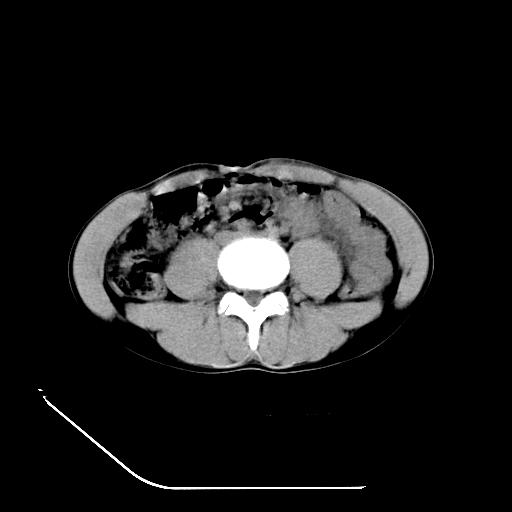

反射性肠郁张是指许多原因造成肠道吸收气体和液 功能障碍,也可造成分泌功能与动力的障碍,以致肠道内有过量的气体和液体潴积,有时只有过量的气体潴积。肠道较舒张,但不扩大,或有部分肠道轻度的扩大,这种情况叫做反射性肠郁张 ,这个病人的肠管扩张太明显了。

提示有肠梗阻的可能性?

我不同意守望可西里老师所说的有输尿管的血液凝积一说,首先从这个图像来看输尿管的走行太偏外了,输尿管是肾盂向下延续的部分,开始在腰大肌的外缘,逐渐向内偏移,接近或越过腰椎横突的外端。而守望可可西里老师所指的这段图像位置太靠外了,且总是伴行在一段肠管的前缘。第二,如果有血液的凝积,可造成肾盂肾盏的扩张积水,而这个病人的肾盂肾盏的形态一直很好。

综上所述,考虑1:左肾挫伤并包膜下血肿2:少量腹腔积液3:肠梗阻的可能

第4点我到考虑为高空坠落后引起的动力性肠梗阻.

病人尿量200ml/24h,是否用反射性肠淤张可以解释。